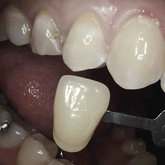

He received his Diploma in Implantology in 2016 from the University of Pretoria, which he passed with Distinction. He is also a member of the International Team for Implantology (ITI), which is based in Switzerland and offers members access to the latest research and cutting-edge techniques.

Porcelain crowns and restorations made in one appointment.

We make it a priority to incorporate the latest in dental technology in everything we do at our practice. ...